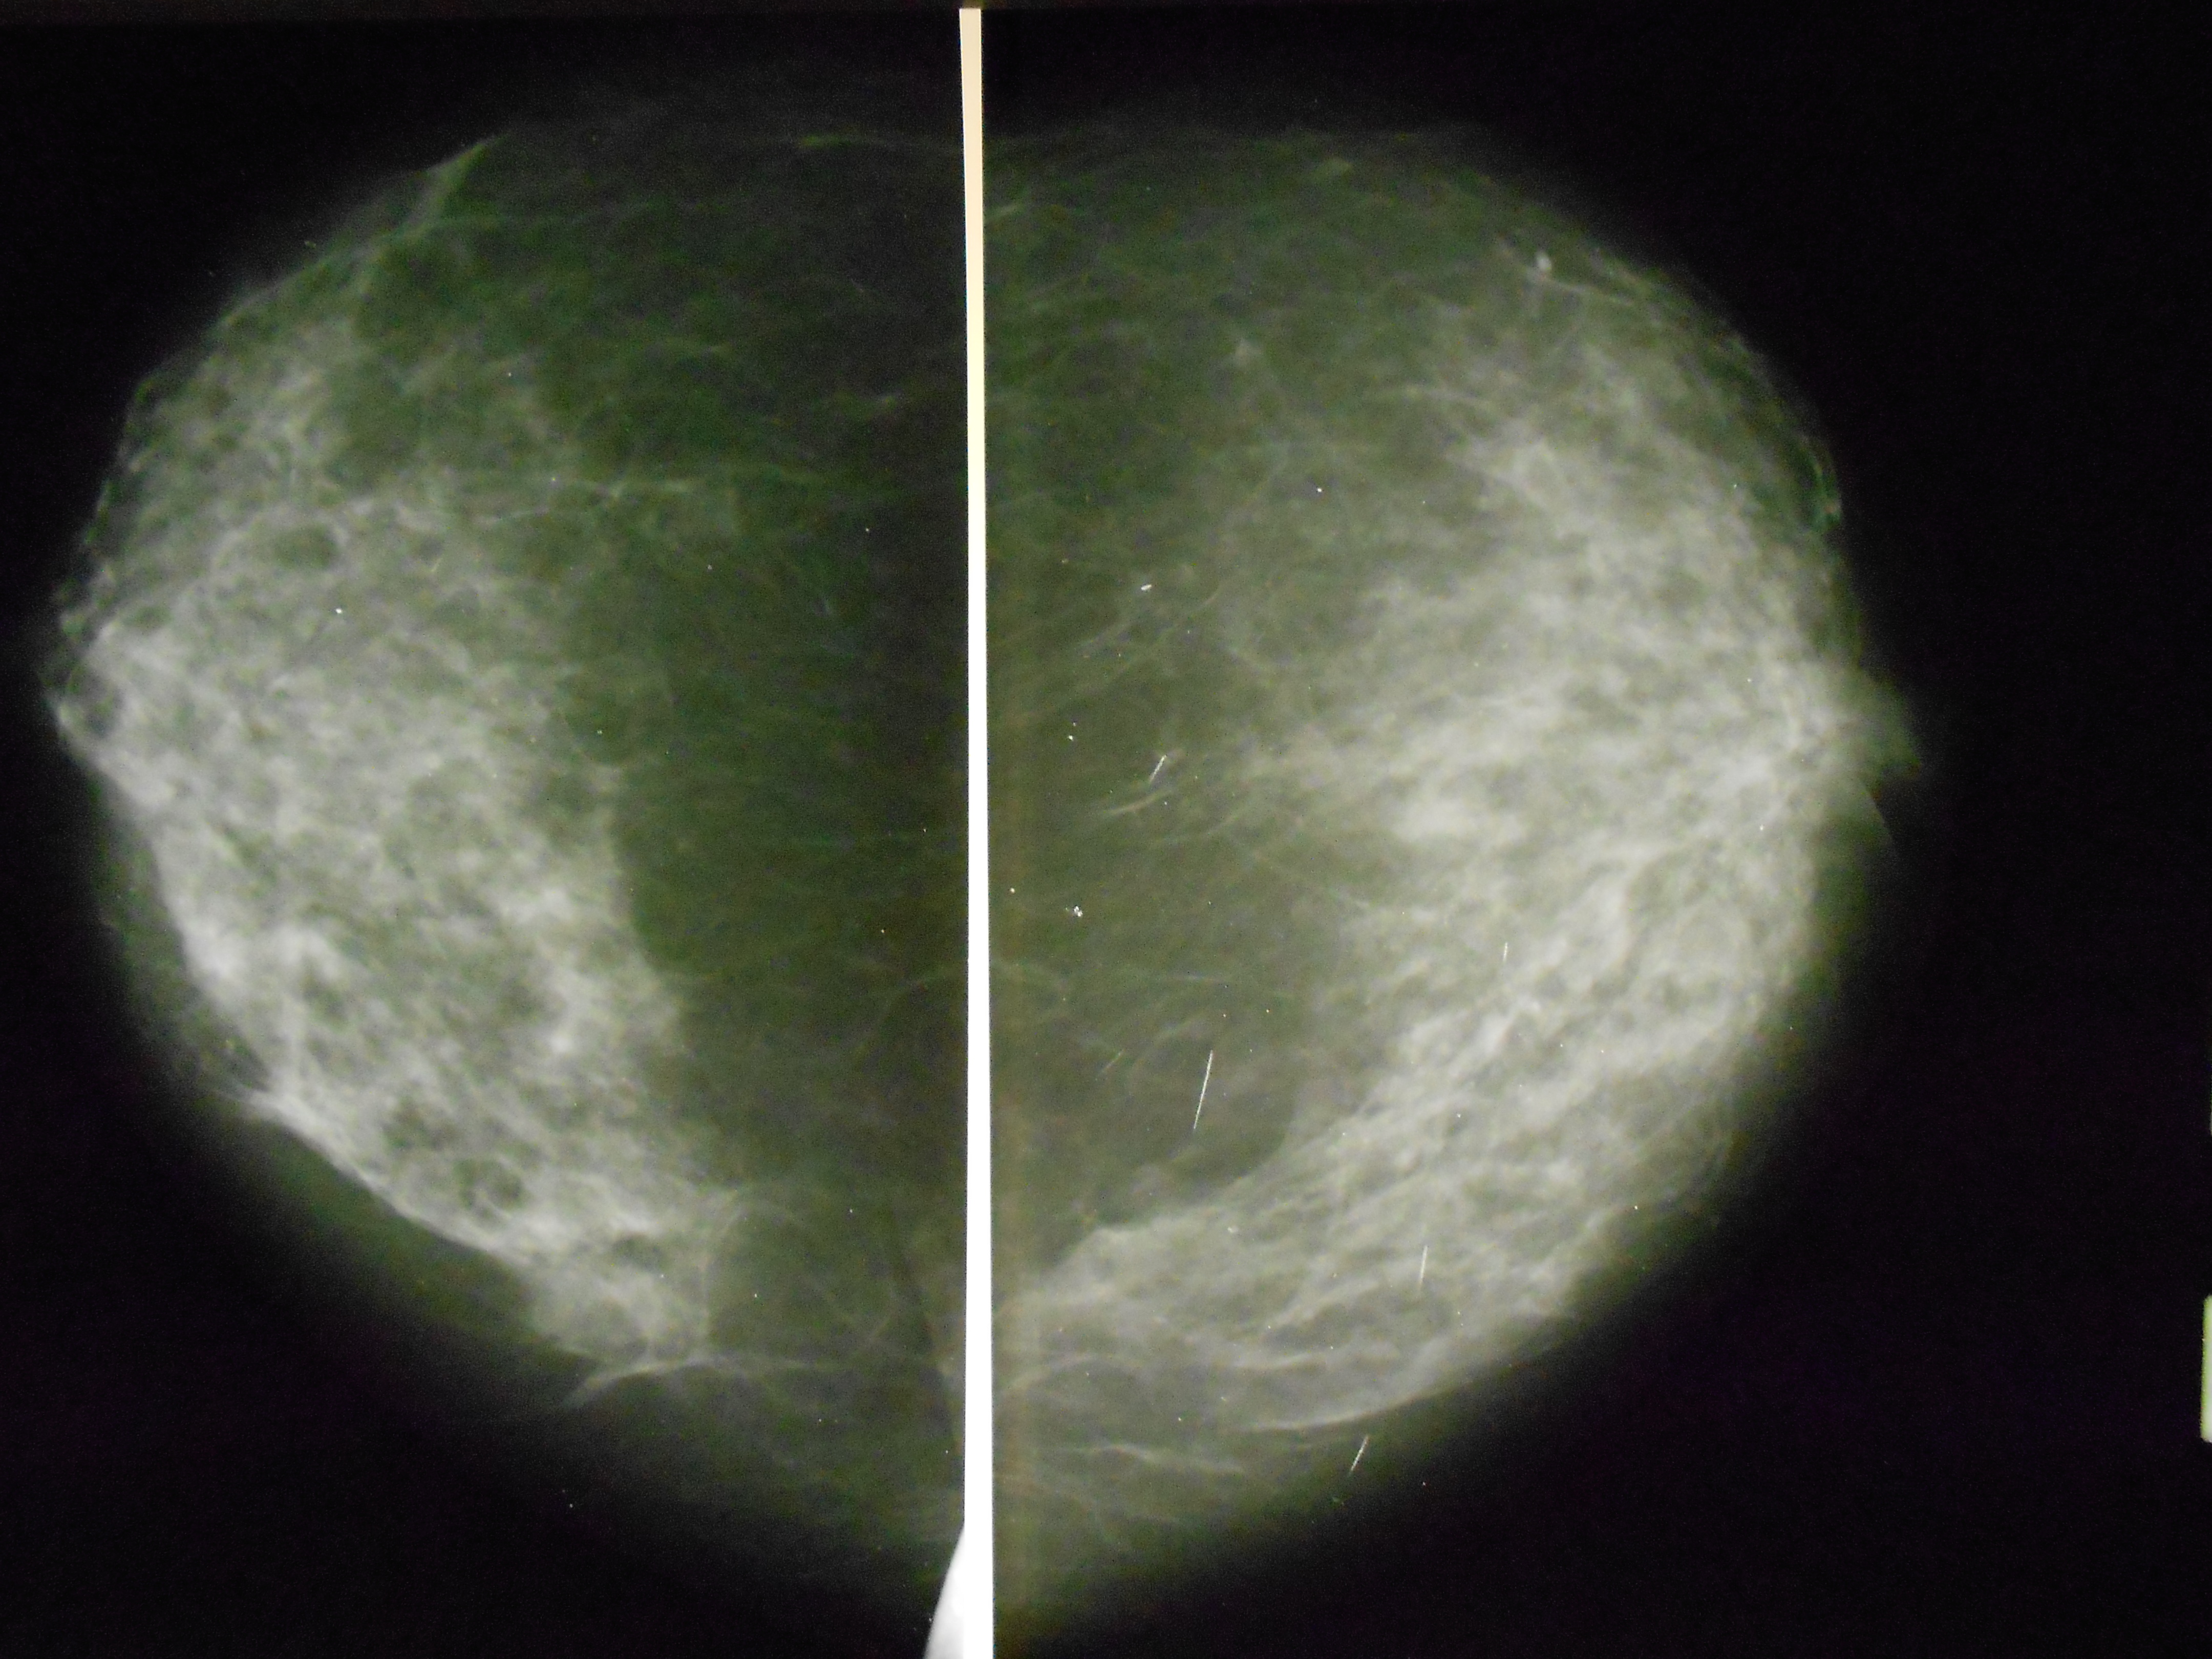

Фиброзно кистозная мастопатия маммограмма

Маммография и ее роль в диагностике фиброаденомы молочной железы

Маммография - это рентгенологическое исследование молочных желез. Оно позволяет выявить различные изменения в тканях, включая фиброаденому. На маммограммах можно увидеть структурные особенности опухоли и отследить ее динамику во времени.